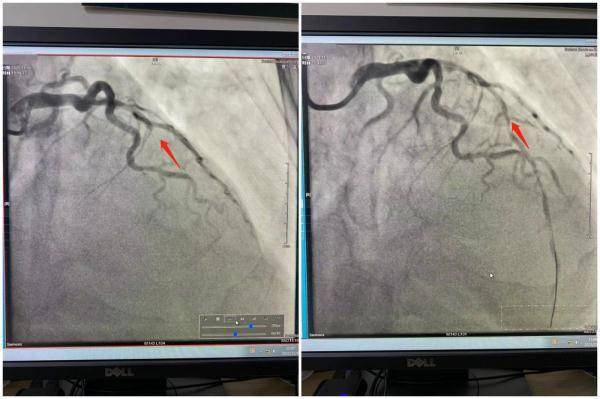

另一位患者周先生今年36岁 。 周先生平时身体良好 , 但他吸烟有十余年 , 每天平均2包 。 近半月来 , 周先生出现间断胸闷、胸痛的症状 , 步行200米便出现不适 , 无法正常生活 。

经过检查 , 医生立即对周先生进行手术治疗 。 术中发现心脏三支血管均有不同程度的狭窄 , 并且有一支血管已经闭塞 。 置入一枚支架后 , 周先生的情况稳定下来 。

文章图片

左:术前 右:术后

图源:苏州高新区人民医院心血管内科